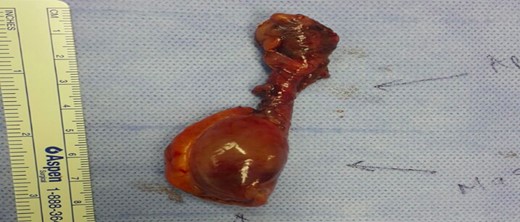

A week later, the patient was seen in the general surgery clinic, still complaining of abdominal pain. CT abdomen was repeated and showed the same findings. A decision was made to admit the patient with a possible diagnosis of an appendicular mucocele or less likely an appendicular carcinoid. A diagnostic laparoscopy with appendectomy and possible right hemi-colectomy was scheduled. Intra-operatively, the appendix was para-caecal and adherent to the caecum with a 3 cm cystic swelling of proximal appendix (Fig. 2). The caecum and ileum were normal and there were no peritoneal deposits. We managed to perform the appendectomy with an intact cystic mass.

Histological examination showed an appendix measuring 7 cm in length and 0.8 cm in diameter with a cystic lesion at the base measuring 3.5 × 2.5 cm2. It had a grey homogenous cut surface invading the appendix wall while the mucosa was unremarkable. The mucosal lining showed elongated and dilated tubules with Goblet cell proliferation with no evidence of dysplasia. The sub-mucosa displayed an area of extensive edema, vascular congestion with focal hemorrhage and abundance of spindle cells, dispersed in a loose fibromyxoid stroma. The sub-mucosal background had copious eosinophils, lymphocytes and blood cells. There was no mitosis, acute inflammation, granuloma, ischemia or vasculitis (Figs 3–6). These findings are consistent with an appendicular IFP (Vanek’s tumor).